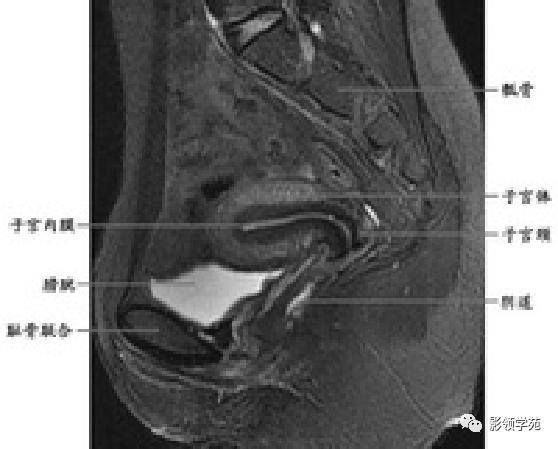

T2WI :

宫颈四层:

高信号---宫颈管黏液

稍高信号---宫颈黏膜皱襞;

低信号---宫颈纤维基质(与宫体JZ连续)

等信号---宫颈肌层

宫颈

T1WI表现为较均匀一致的稍低信号

高分辨率T2WI可看到4层结构

最内层-高信号粘液

粘膜层(柱状上皮)-高信号,低于粘液信号

纤维间质(结合带)-低信号

肌层-中等信号

阴道壁

阴道粘膜 为复层鳞 状上皮

T1WI 呈中等稍低信号

T2WI内带:高信号(上皮、粘液)

外带 :低信号